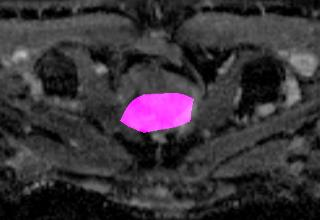

Weakly Supervised Semantic Segmentation (WSSS) relying only on image-level supervision is a promising approach to deal with the need for Segmentation networks, especially for generating a large number of pixel-wise masks in a given dataset. However, most state-of-the-art image-level WSSS techniques lack an understanding of the geometric features embedded in the images since the network cannot derive any object boundary information from just image-level labels. We define a boundary here as the line separating an object and its background, or two different objects. To address this drawback, we are proposing our novel ReFit framework, which deploys state-of-the-art class activation maps combined with various post-processing techniques in order to achieve fine-grained higher-accuracy segmentation masks. To achieve this, we investigate a state-of-the-art unsupervised segmentation network that can be used to construct a boundary map, which enables ReFit to predict object locations with sharper boundaries. By applying our method to WSSS predictions, we achieved up to 10% improvement over the current state-of-the-art WSSS methods for medical imaging. The framework is open-source, to ensure that our results are reproducible, and accessible online at https://github.com/bharathprabakaran/ReFit.